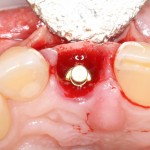

Устанавливается имплантат Astratech (Dentsply Implants):

Для аугментации также используем Bio-Oss Collagen 100 mg, нарезаем его по размеру с помощью скальпеля и позиционируем в лунках щечных корней:

На имплантат ставим формирователь, ушиваем лунку. Напомню, что любой биоматериал должен быть герметично запечатан в ране (фактор успеха III). В противном случае, от него больше вреда, чем пользы:

Совсем уж стягивать края раны не нужно (если бы мы использовали обычный Bio-Oss, то это было бы необходимо). Отличие Bio-Oss Collagen еще и в том, что он не размывается при кровотечении.